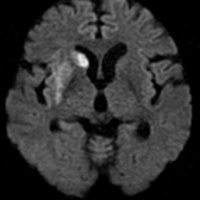

脳の中にアミロイドβタンパクという異常な物質の蓄積が認められ、その後タウタンパクが神経細胞内にたまりその後神経細胞が死んで行きます。海馬周辺の細胞が主に障害されるため、記憶障害が早期から認められるのが特徴です。アミロイド仮説と言われていますが、なぜそのような物質がたまりやすい人がいるのかはまだよくわかっていません。

軽度のもの忘れ症状で認知症の一歩手前のような状態を軽度認知機能障害といいます。年齢と共に記憶力が低下することは誰でもあると思います。脳のMRI検査にて海馬に萎縮がみられる場合は、今後アルツハイマー病に進展していく可能性もあると指摘されています。

心配の方は一度脳のMRI検査をしてみることをお勧めいたします。

アルツハイマー病は急に始まるわけでなく、10年ぐらいかけて少しずつ進行してきて症状がでてくると言われています。早めの予防が大切です。